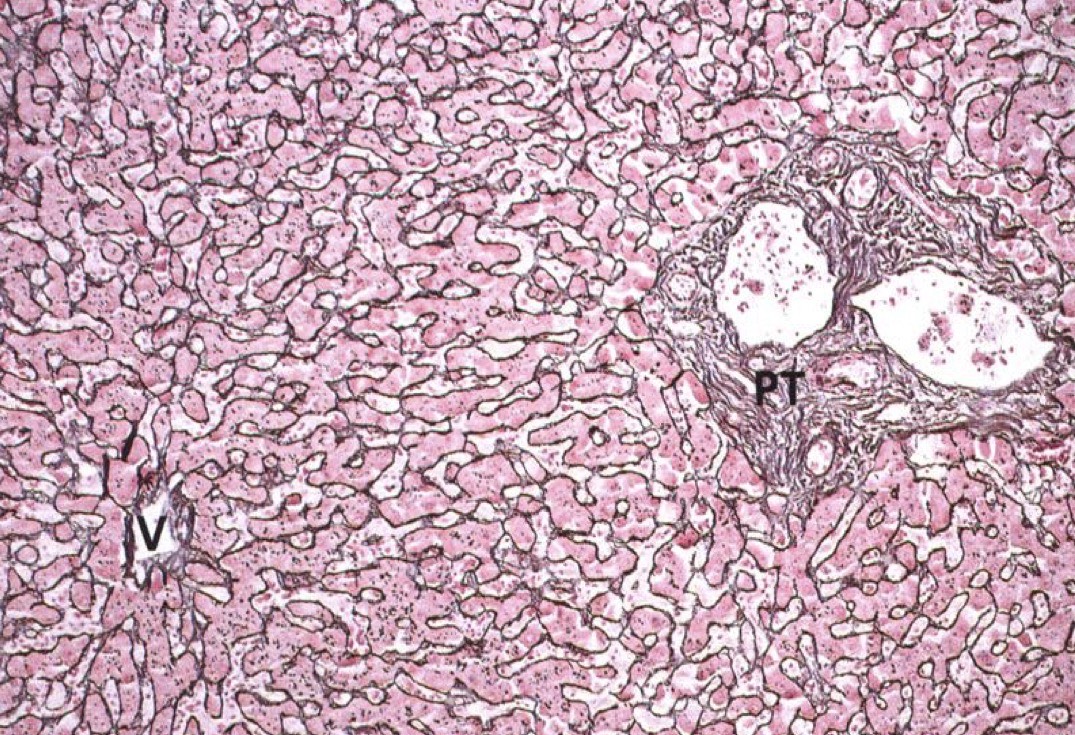

Identify the Organ and Structures?

Liver; Lobule w/ Central vein, surr by Hepato and Sinu, Portal triads in corners